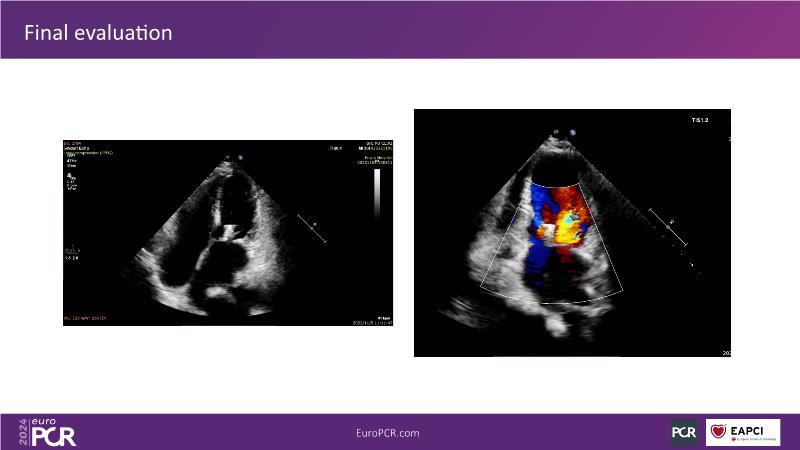

Watch this session to gain insights into the clinical evidence of mitral TEER therapy for the Asian population, learn techniques for implanting a MitraClip in patients with challenging anatomy, and understand how to use the four clip sizes for optimal outcomes. The session also covers educational aspects of clipping in dextrocardia, the benefits of reserve bending of the transseptal needle for tenting and puncture, new steering maneuvers for dextrocardia patients, and the importance of understanding anatomy and collaborating closely with the echo team for success.